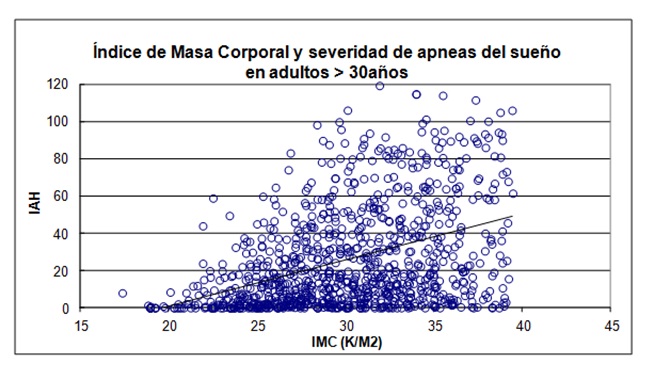

El peso corporal aumentado fue un hallazgo frecuente (promedio 95.5 ± 24.5 kg). Resultó en un índice de masa corporal (IMC) promedio de 34,6 ± 8,1 kg/m2. Se analizó a la obesidad como factor de riesgo predictor de la severidad de las apneas del sueño. Se excluyó de este análisis a los pacientes con IMC > de 40 Kg/m2, para no incluir a los pacientes con síndrome de hipoventilación-obesidad. Existió una correlación significativa, aunque con importante dispersión de valores, entre el índice de masa corporal y el índice de apneas-hipopneas por hora de sueño (r2 = 21,1%, p < 0.001). En pacientes menores de 30 años esta correlación se mantuvo (r2 = 21,9%, p < 0.0004) (Figura 8) (Figura 9).

Figura 8: En pacientes adultos, relación entre el índice de masa corporal yel índice apneas + hipopneas del sueño.